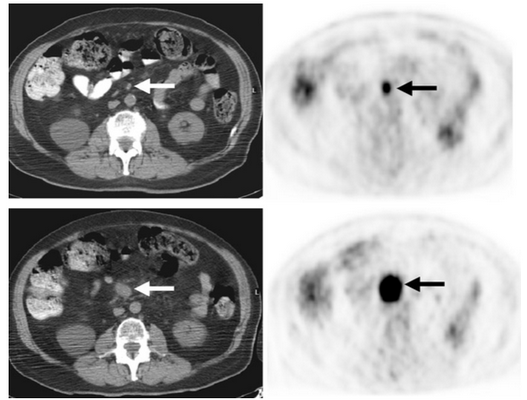

Первые четыре изображения соответствуют первичному исследованию. Вторичное ПЭТ/КТ выполнено спустя 4 месяца.

Снимки спустя 4 месяца после первого исследования. Накопление 18f-FDG 1,2х1,5 см мезентериального лимфатического узла (указано стрелками). На последних двух изображениях узел также гиперметаболический размером 3,8х4,0 см с накоплением 18f-FDG, что характерно для лимфом

Панникулит — прогрессирующее поражение подкожной жировой клетчатки воспалительного характера, приводящее к разрушению жировых клеток и замещению их соединительной тканью с образованием узлов, бляшек или инфильтратов. При висцеральной форме панникулита происходит поражение жировых клеток печени, поджелудочной железы, почек, жировой клетчатки сальника или забрюшинной области.